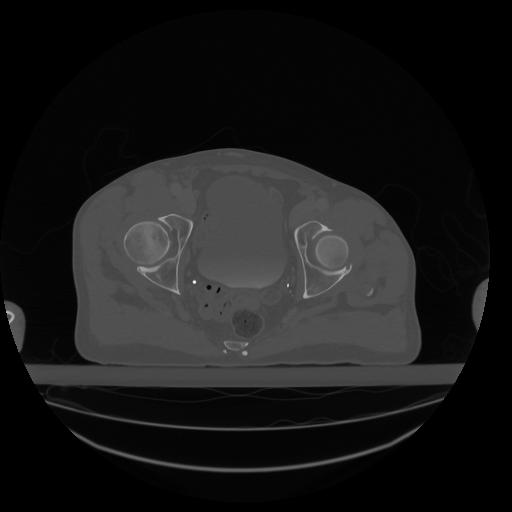

34 CUERPO,CE,Vol,1.0,CUERPO,,